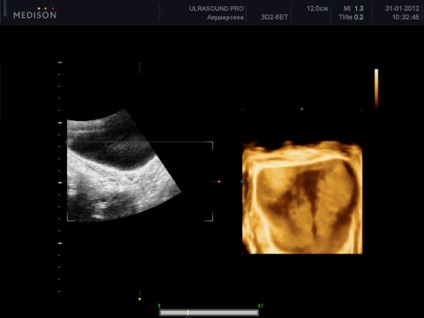

uter ultrasunete 3d

ultrasunete tridimensională a uterului produce indisponibile în proiecție cu ultrasunete convențională și este utilă în evaluarea contururile exterioare ale uterului, și poate detecta anomalii în structura, în special în uter. combinație 3d gidrotubatsii cu ultrasunete poate imagine uter detaliu mare (de exemplu, este foarte valoros atunci când detectarea polipi endometriali). Volumul rezultat al uterului în timpul imaginii tridimensionale pot fi supuse la ultrasunete postprocesare și să obțină mai multe felii în diferite proiecții. O astfel de ultrasunete a uterului este, de asemenea, numit imagistica cu ultrasunete. Astfel, combinația dintre o ecografie bidimensional convențională a uterului și trehmrnogo oferă noi posibilități în imagistică și diagnostic, fiind imposibil de atins folosind ultrasunete conventionale. Cel mai probabil, în viitorul apropiat, astfel de studii vor deveni norma in timpul ecografiei a uterului si apendicelor.